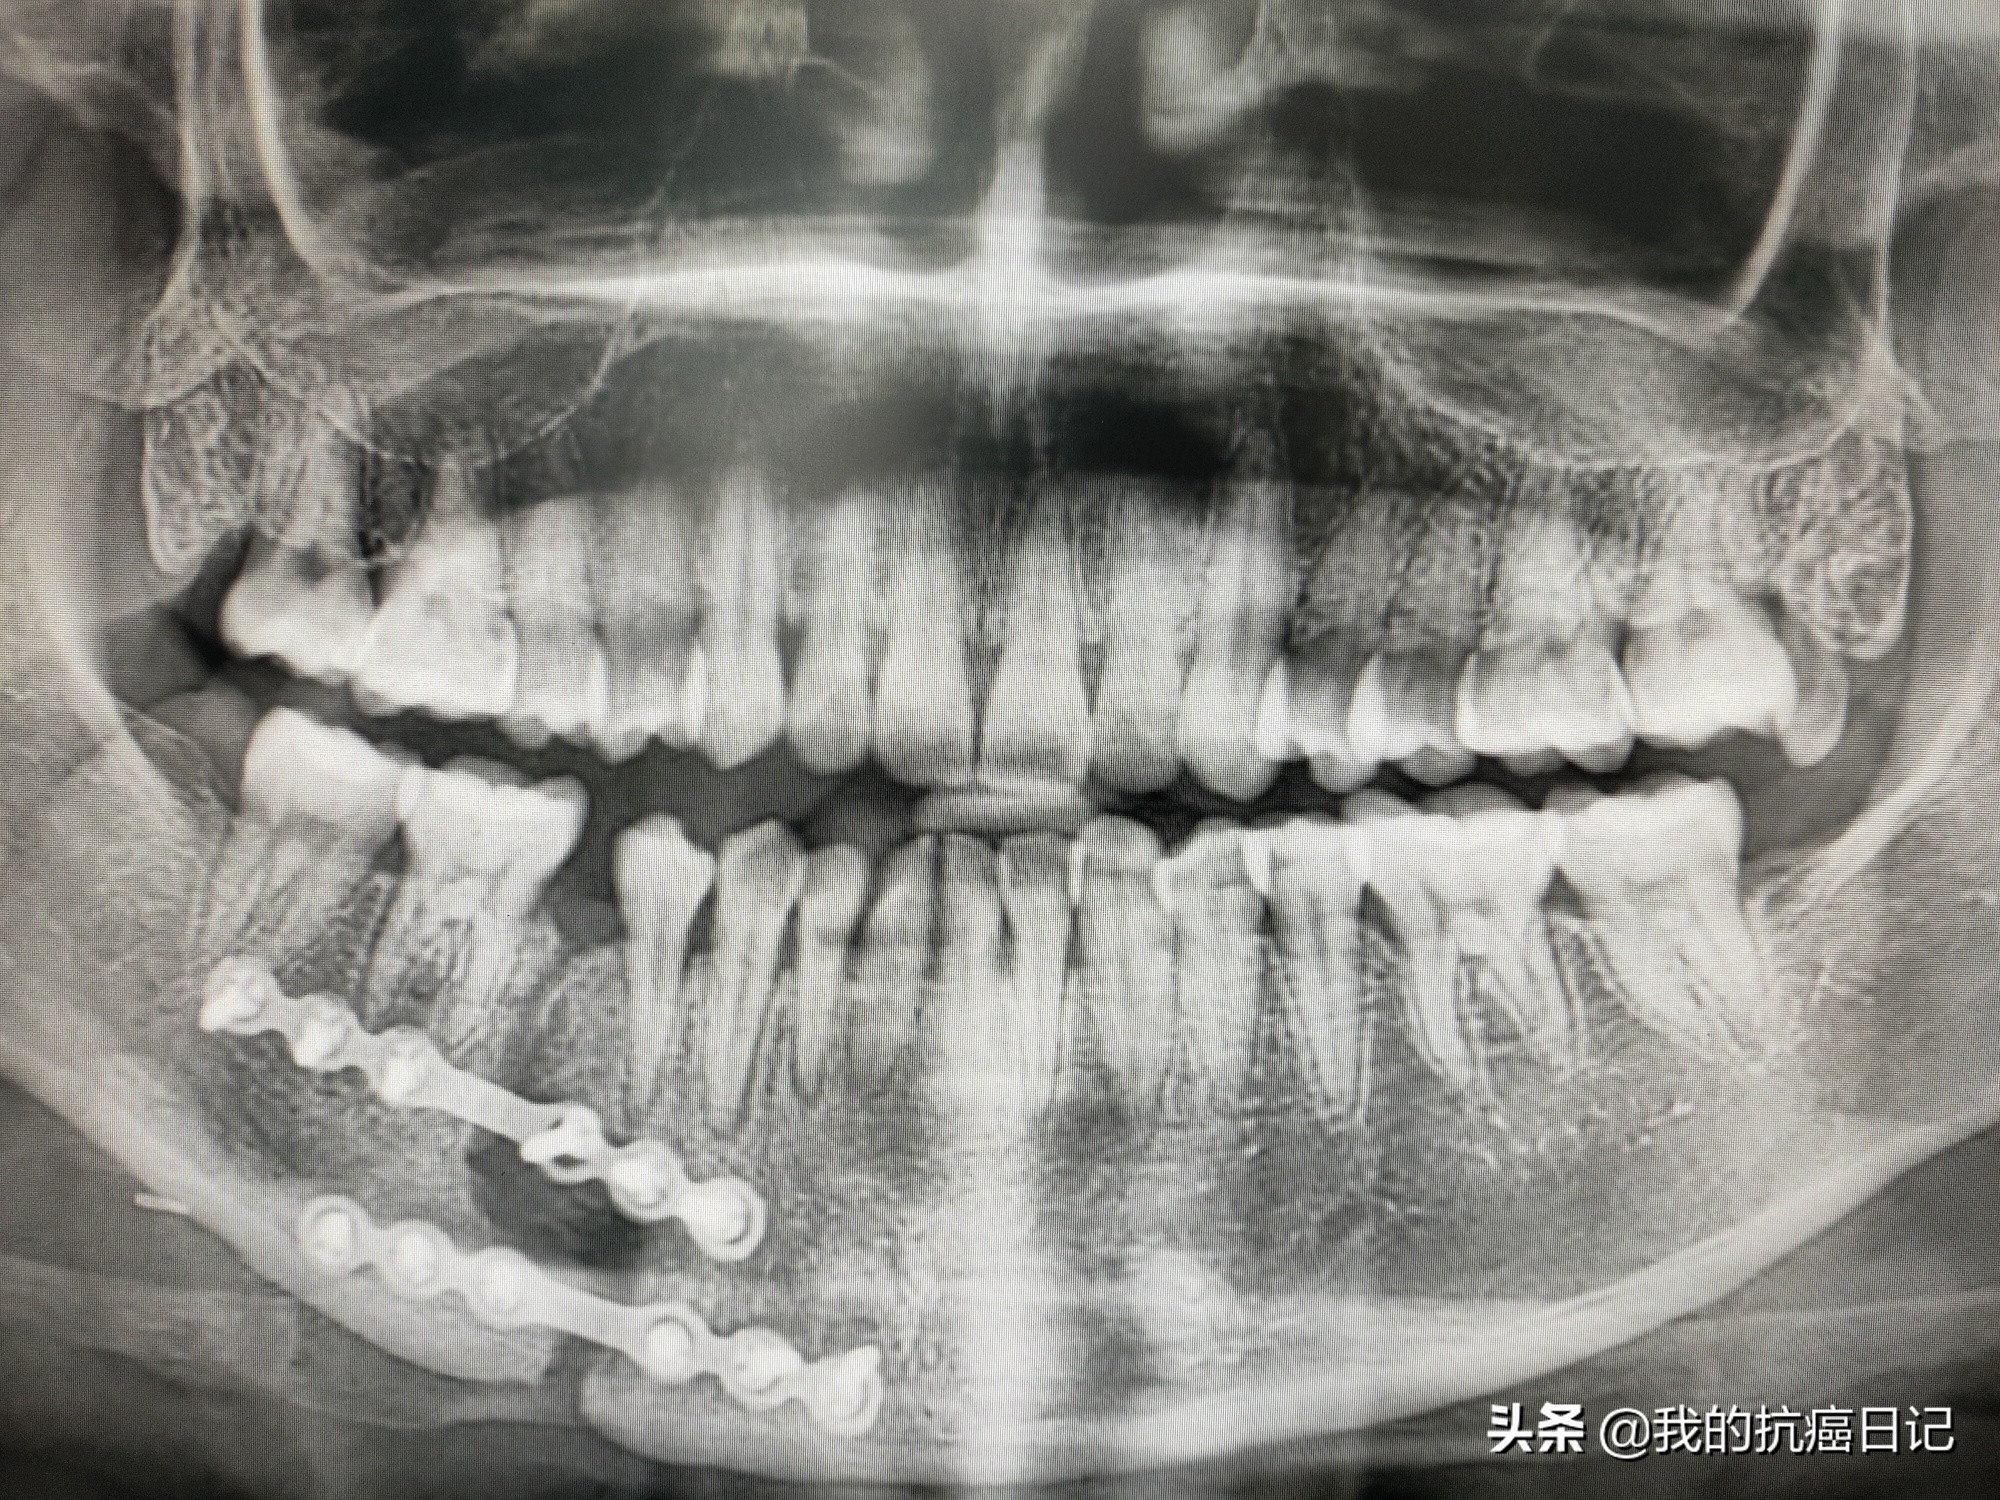

From mybrokenjawtrauma.blogspot.com

My Broken Jaw Trauma October 2014 Jaw Always Cracks When I Open My Mouth tmj disorders can also cause a clicking sound or grating sensation when you open your mouth or chew. If your jaw starts to bother you with clicks and pops while you eat or when you yawn, you might start to worry. painful clicking or popping when you open and close your mouth is one of the biggest symptoms,. Jaw Always Cracks When I Open My Mouth.

From inf.news

Tongue cancer girl A year after opening my jaw, I still have a big crack in my jaw iNEWS Jaw Always Cracks When I Open My Mouth tmj disorders can also cause a clicking sound or grating sensation when you open your mouth or chew. If your jaw starts to bother you with clicks and pops while you eat or when you yawn, you might start to worry. These joints connect the jawbone to the skull,. jaw popping can be a painful sensation that’s caused. Jaw Always Cracks When I Open My Mouth.